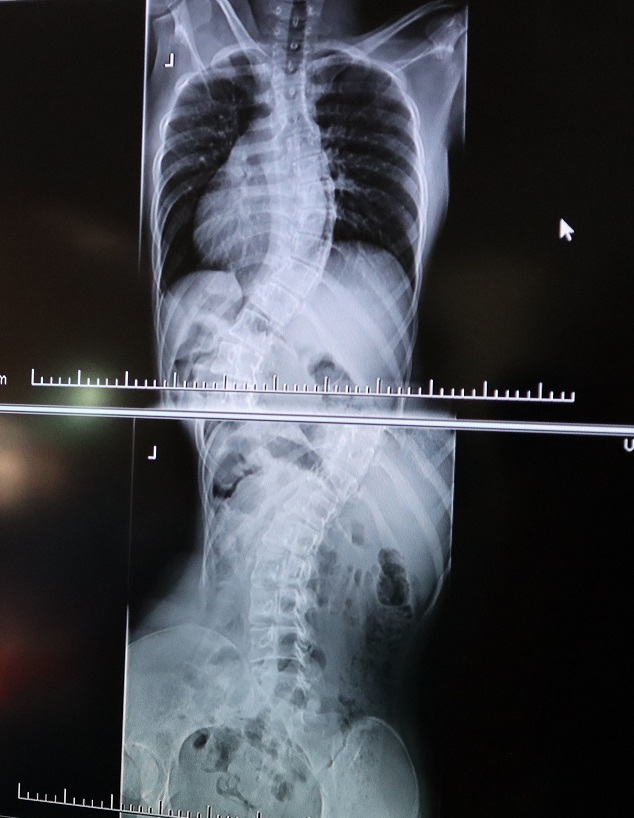

Vladyslava trpí idiopatickou skoliózou, ktorá spôsobila výrazné zakrivenie jej chrbtice. Ako priblížil primár oddelenia pediatrickej ortopédie a vedúci lekár spondylochirurgie FNsP Žilina Juraj Popluhár, v Žiline zrealizujú ročne približne 100 až 115 operácií rôznych deformít chrbtice celého vekového spektra. Mladá ukrajinská pacientka čakala na termín výkonu v štandardnom poradovníku a operáciu absolvovala v stredu 10. augusta 2022. „Zhoršujúce sa nálezy sú bežne riešené operačne pri zakrivení od 35 až 40 stupňov, v tomto prípade mala pacientka skoliózu v pokročilom štádiu so zakrivením nad 70 stupňov, kedy nejde o estetickú pomoc, ale o zdravotnú indikáciu. Ochorenie ovplyvňuje vitálnu kapacitu pľúc, obehový systém, opotrebenie platničiek a tiež môže spôsobovať kardiologické ťažkosti,“ priblížil J. Popluhár s tým, že pri štvorhodinovej operácii 16-ročnej študentky zvolili zadný prístup. „Chrbticu sa nám podarilo úspešne zreponovať, vyrovnať a zastabilizovať definitívnym fixátorom, ktorý ostáva v tele pacientky. Jej život však neobmedzí, naopak zlepší sa jeho kvalita i zdravotný stav, ktorý by sa bez operačnej liečby v ďalších rokoch výrazne zhoršoval a priniesol mnohé závažné problémy,“ doplnil primár žilinskej detskej ortopédie. Voperovaný implantát pozostáva podľa jeho slov z dvoch chróm-kobaltových tyčí a 24 titánových skrutiek.